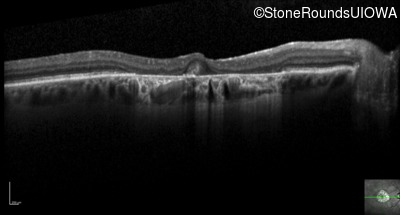

Optical Coherence Tomography - Left - 20/80 +1

Exemplar / OCT Stack